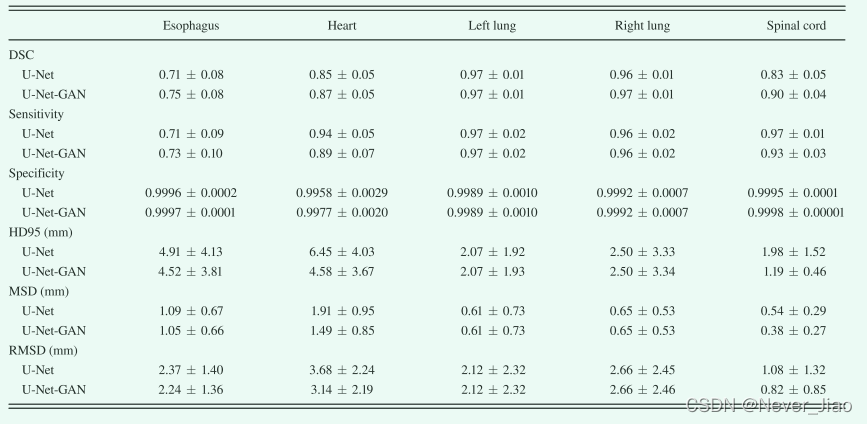

定量评估结果总结在图 5 和表 I 中。图 5 显示了对所有 35 名患者进行计算的六个评估指标——DSC、敏感性、特异性、HD95、MSD 和 RMSD,其平均值和标准差列于表中 I. 如图 5 和表 I 所示,所提出的方法在左肺、右肺和脊髓上实现了优异的分割精度,分别为 0.97、0.97 和 0.90 的平均 DSC,平均 HD95 为 2.07、2.50 和 1.19 毫米,所有平均 MSD 小于 1 毫米。由于图像对比度降低,心脏分割不如肺和脊髓分割简单。定量评估表明,所提出的方法与心脏描绘的基本事实非常吻合。平均DSC为0.87,平均HD95为4.58 mm,平均MSD为1.49 mm。在CT图像上,食管是五个器官中对比度最低的,因此最难描绘。提出的方法在食道分割上获得0.75±0.08 DSC、4.52±3.81 mm HD95和1.05±0.66 mm MSD。灵敏性评估真实的OAR体积与从该方法获得的体积重叠,而特异性量化真实体积之外的重叠部分。该方法的平均分割灵敏度为0.74–0.97,双侧肺最高,食道最低。这五种器官的特性几乎是一致的。五个器官的平均RMSD范围为0.8至3.1 mm。

U-Net-GAN 通过引入鉴别器改进了 U-Net 方法。为了提供具体的改进展示,我们进行了一个留一法实验来比较 U-Net 在有和没有对抗性网络的情况下产生的结果,如表 III 所示。 UNet 的所有参数都是根据提供最佳性能的参数设置的。如表所示,在对抗网络的帮助下,大多数评估指标都得到了改善(DSC、Specificity 和 Sensitivity 增加;HD95、MSD 和 RMSD 减少)。

Table3. U-Net 和 U-Net 生成对抗网络 (U-Net-GAN) 之间的分割比较,所提出的方法,具有Dice相似系数 (DSC)、灵敏度、特异性、95% Hausdorff 距离的均值和标准差 ( HD95)、平均表面距离 (MSD) 和剩余均方偏差 (RMSD)。